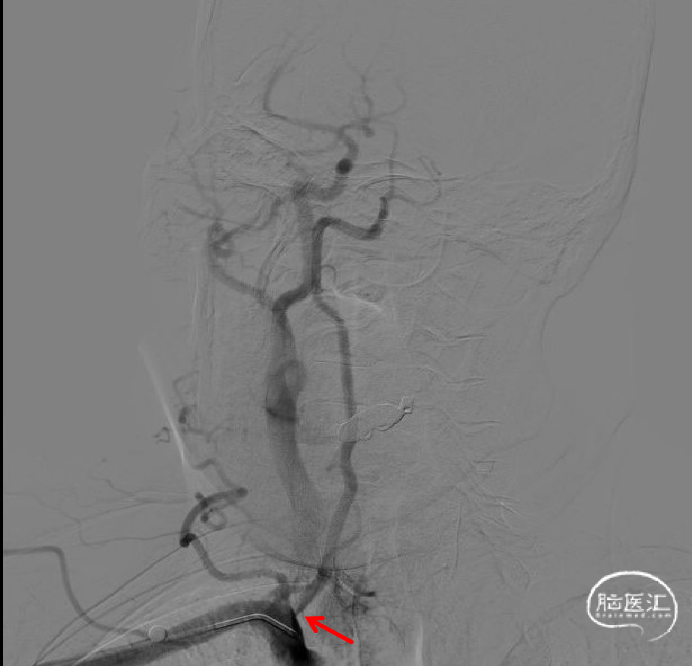

沿泥鳅导丝将6F 95cm远端通路导引导管送至右侧椎动脉开口近狭窄处,撤出泥鳅导丝,在路途下,将0.014inch 180cm导引导丝超选至右侧椎动脉V3段远端,沿微导丝将Bridge椎动脉雷帕霉素靶向洗脱支架送至右侧椎动脉V1段狭窄处,支架释放之前再次通过显影点,确认支架位于合适位置,排气后,以10-15s/atm缓慢加压至10atm打开输送系统球囊以扩张支架。

造影示支架完全覆盖狭窄段,与血管壁贴合良好。复查脑血管造影颅内远端血流通畅。

术后影像